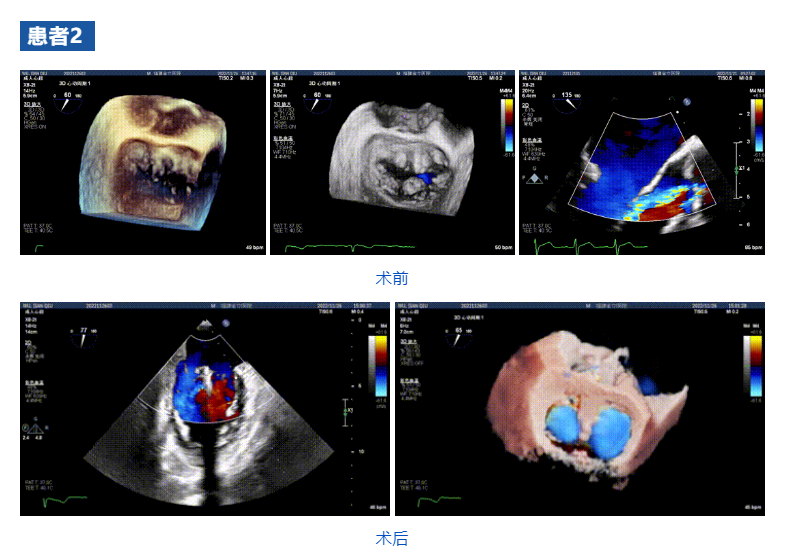

接受治療的三例患者均為器質(zhì)性重度二尖瓣反流(DMR)患者,術(shù)前超聲提示二尖瓣后葉脫垂伴4+反流,左室舒張功能減退。郭延松教授攜同團(tuán)隊(duì)成員陳新敬副教授和洪景宣、方明程、楊清勇主治醫(yī)師、心外科丁杭主任以及超聲科賴寶春、葉振盛主治醫(yī)師共同進(jìn)行病情討論??紤]到患者高齡、基礎(chǔ)疾病多、STS評分高,為外科手術(shù)極高危患者,不適合進(jìn)行外科開胸二尖瓣手術(shù),因此決定為患者實(shí)施經(jīng)導(dǎo)管緣對緣修復(fù)介入術(shù)(JensClip經(jīng)導(dǎo)管瓣膜夾系統(tǒng))。

在浙江大學(xué)醫(yī)學(xué)院附屬第二醫(yī)院王建安教授團(tuán)隊(duì)的支持下,手術(shù)經(jīng)股靜脈-房間隔入路,采用全身麻醉插管,在TEE和DSA引導(dǎo)下完成房間隔穿刺。置入JensClip瓣膜夾系統(tǒng)后,在左房調(diào)整瓣膜夾的位置和軸向,后進(jìn)入左室,在TEE引導(dǎo)下捕捉二尖瓣前后瓣葉,并關(guān)閉瓣膜夾。經(jīng)TEE反復(fù)確認(rèn)手術(shù)效果后最終鎖定并釋放瓣膜夾。術(shù)后即刻超聲顯示瓣膜夾位置穩(wěn)定,功能良好,二尖瓣反流由術(shù)前4+減少至微量,手術(shù)圓滿成功。